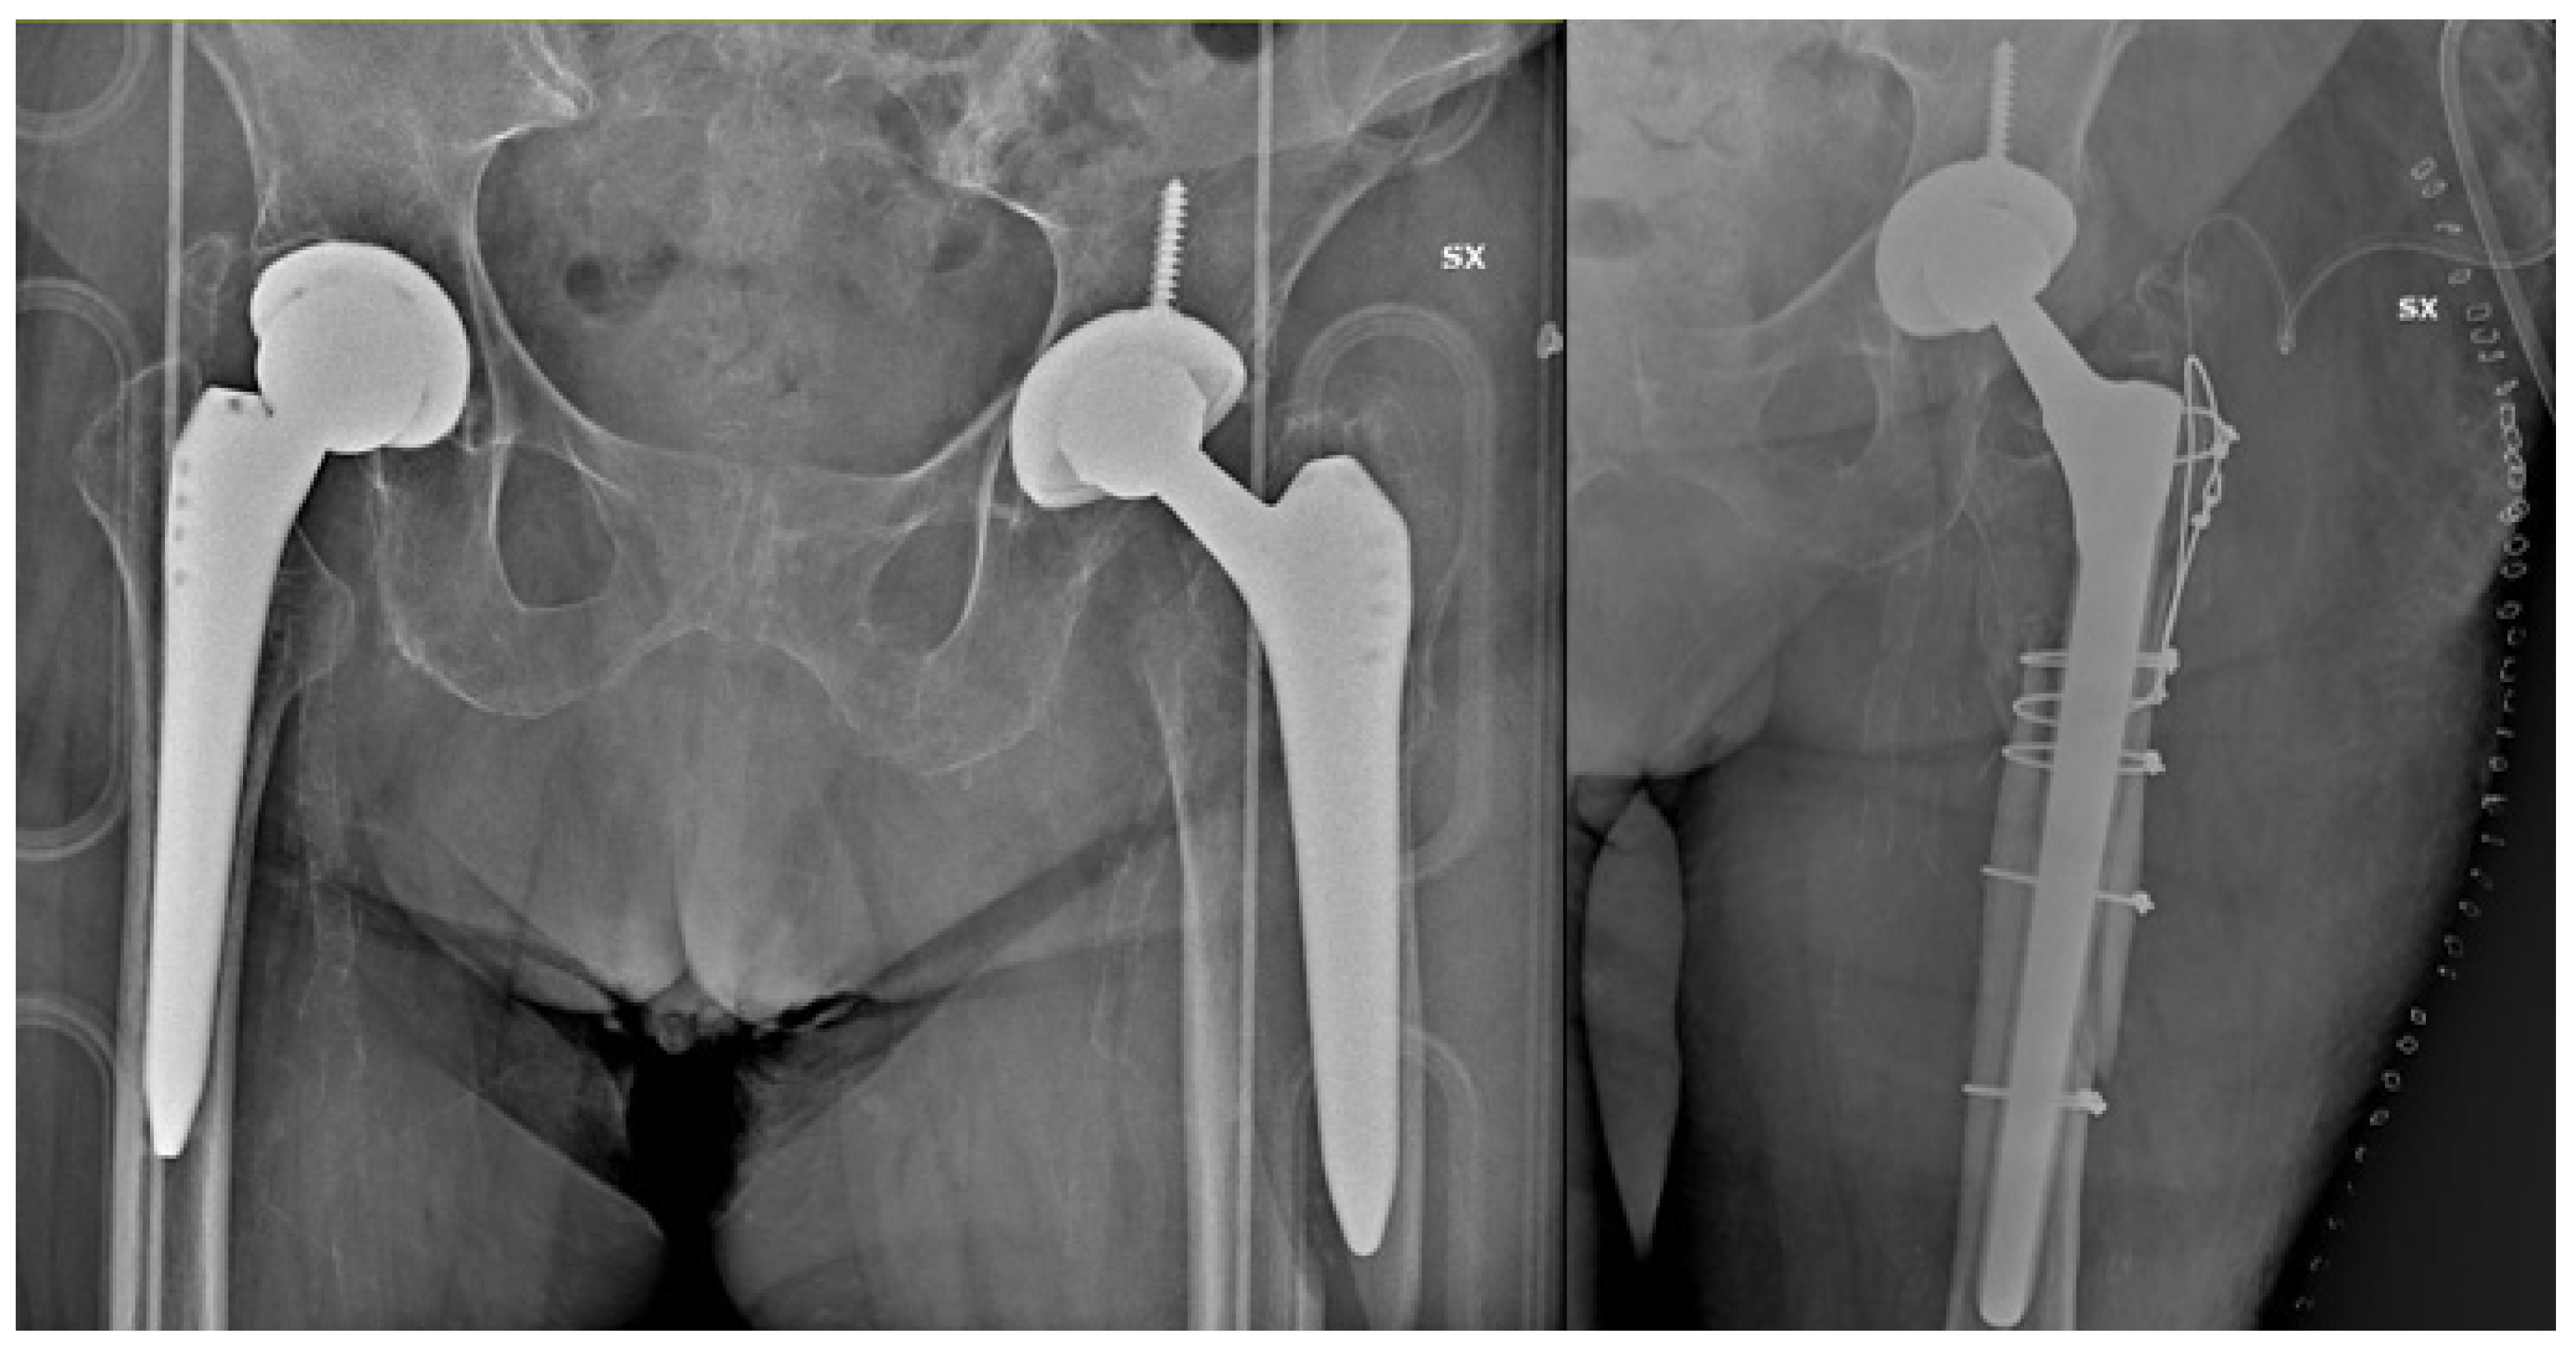

Periprosthetic Hip Fractures around the Stem: Can the Stem Design Affect Fracture Features?

2. Material and Methods

3. Results